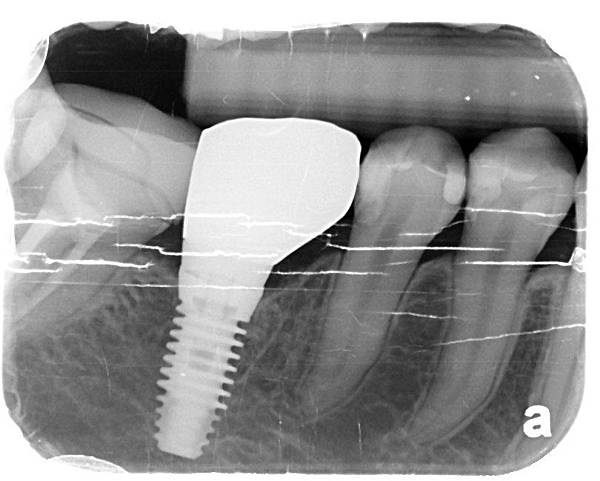

右下大臼齒因為嚴重蛀牙需拔除

拔牙後同時做植牙動作

X光片系列

X光片系列

下顎第一大臼齒拔牙同時合併人工植牙